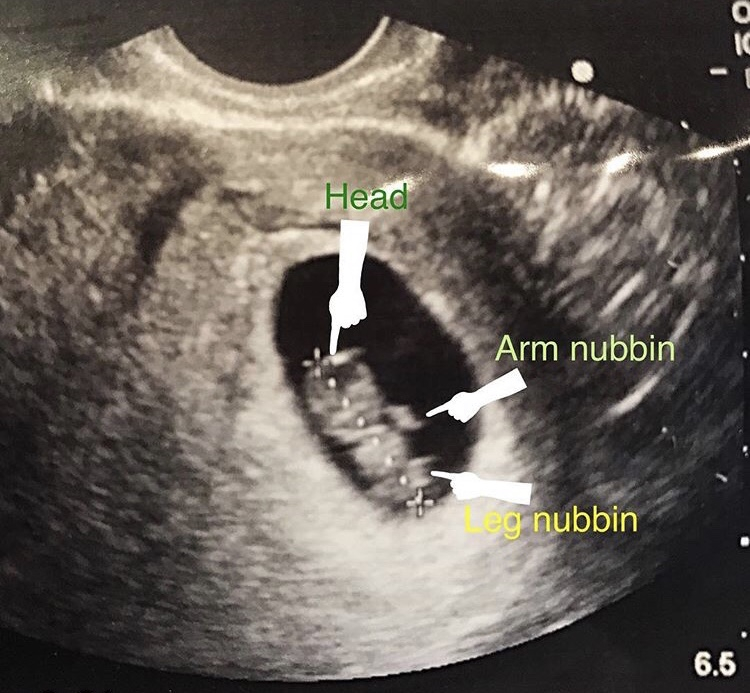

This was at 7w3d, transvaginal US. Doctor did it in his office with his little old school machine, that's why it's so grainy lol! Saw heartbeat and baby wiggling! Due 7/21, this is my second pregnancy, first one ended in ectopic with rupture last June